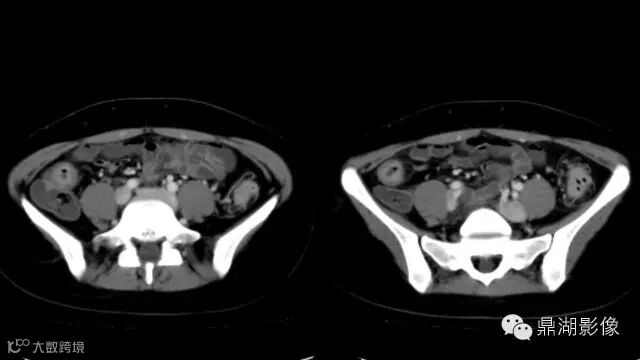

what's the meaning of fat halo sign?

粘膜下水肿或脂肪沉积,可致肠壁内呈低密度层(halo征),其最初用来描述溃疡性结肠炎,是良性肠道病变的结果,无特异性,也可存在于放射性肠炎,移植-受体疾病和慢性缺血性肠炎以及单性的肥胖症患者。

Fat halo aslo can be seen in normal terminal ileum.

It is the comb sign the most specific sign for crohn's disease.